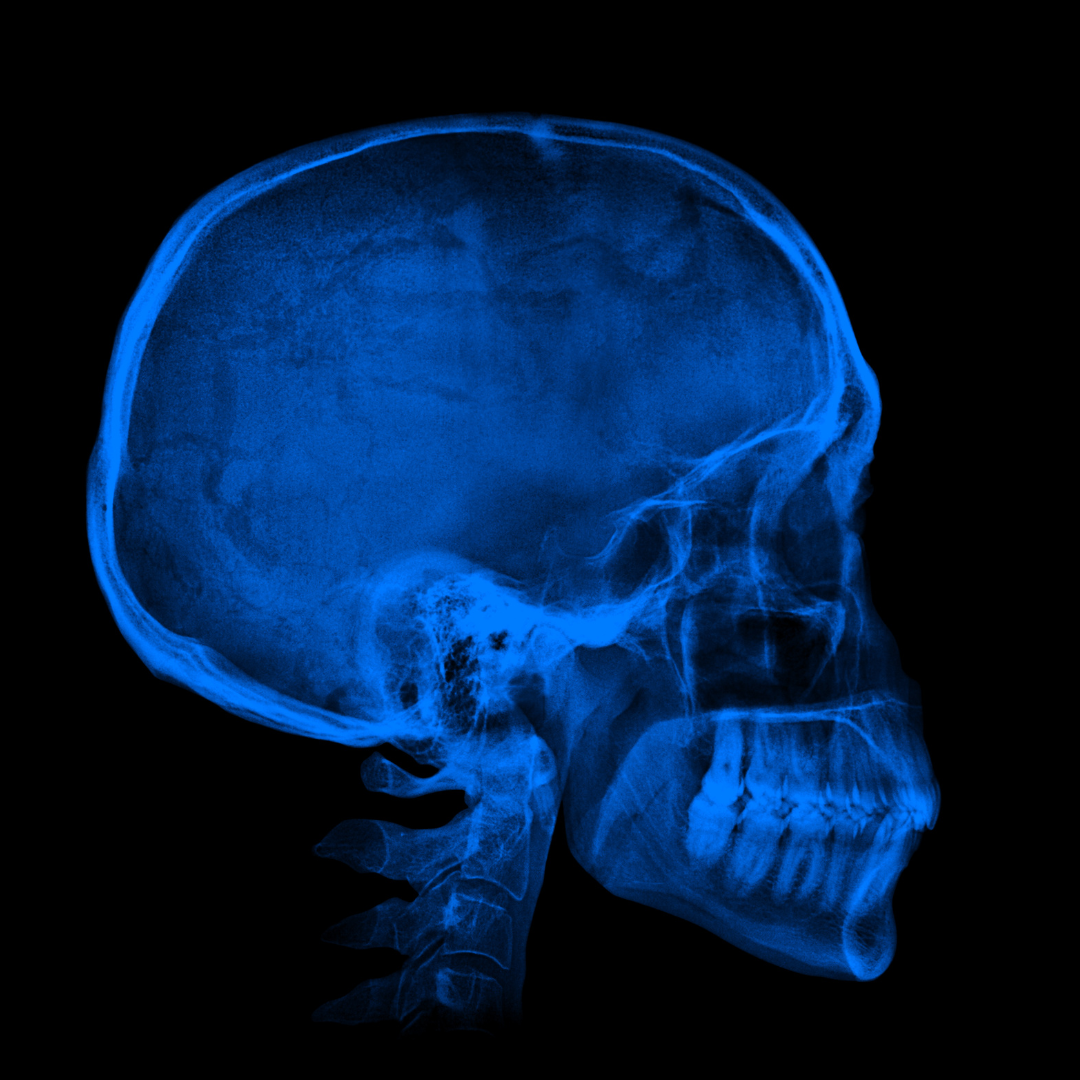

Рентгенография черепа и позвоночника: изображение и диагностика